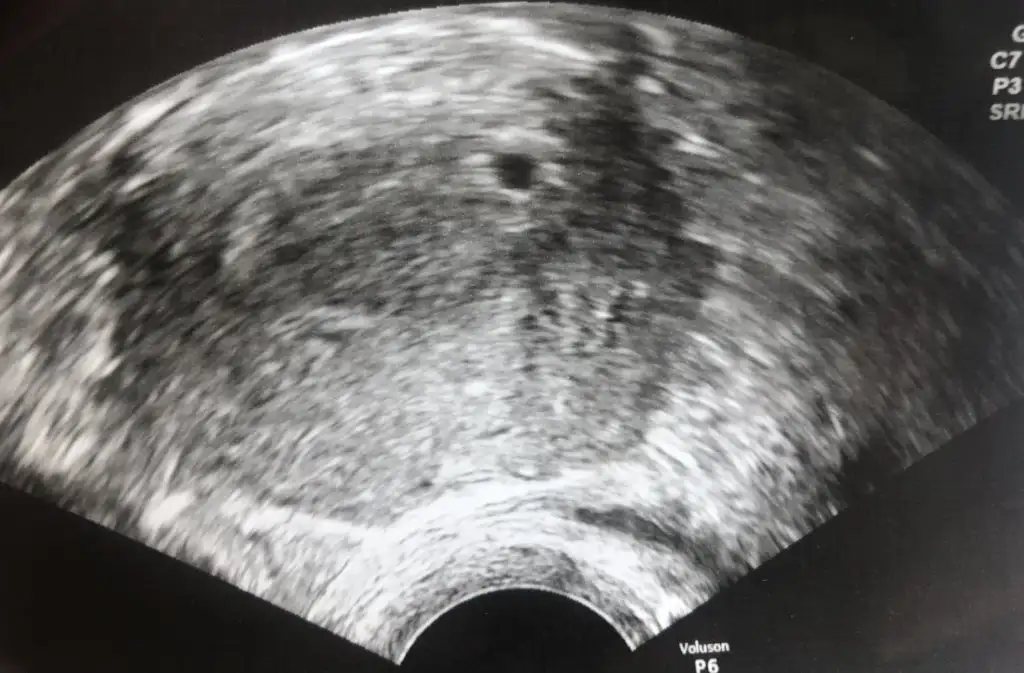

Çok güzelMerhaba minnak anneler bizde kesemizi gördük. Ama dr ölçmedi ya sizce çok küçük değil mi 5+2yiz şu an 3 gün önce son beta 1400 cicarıydı.anlayan varsa yorum yapabilir mi lütfen

Harika demekki 5+2 ultrason için uygun bende haftaya randevu oldum 5+3 olacak kalp atışını duydunuz mu ?Merhaba minnak anneler bizde kesemizi gördük. Ama dr ölçmedi ya sizce çok küçük değil mi 5+2yiz şu an 3 gün önce son beta 1400 cicarıydı.anlayan varsa yorum yapabilir mi lütfen

Aynıyız :)) Benim de 5+2 bugün. Geçtiğimiz salı gördüm ben keseyi. Pazartesi değerim 972 idi. Salı rahatsızlanınca acile gittim. Orada baktı kadın doğumcu. 0.43 cm yazıyor ultrason kağıdında. Büyüklük değil de süreçteki gelişimi önemli bildiğim kadarıylaMerhaba minnak anneler bizde kesemizi gördük. Ama dr ölçmedi ya sizce çok küçük değil mi 5+2yiz şu an 3 gün önce son beta 1400 cicarıydı.anlayan varsa yorum yapabilir mi lütfen

Merhabalar bende programa göre 5+3üm keseyi dün gördüm beta değerim de 2088di :) inşallah sağlıkla kavusuruz bebislerimizeAynıyız :)) Benim de 5+2 bugün. Geçtiğimiz salı gördüm ben keseyi. Pazartesi değerim 972 idi. Salı rahatsızlanınca acile gittim. Orada baktı kadın doğumcu. 0.43 cm yazıyor ultrason kağıdında. Büyüklük değil de süreçteki gelişimi önemli bildiğim kadarıyla